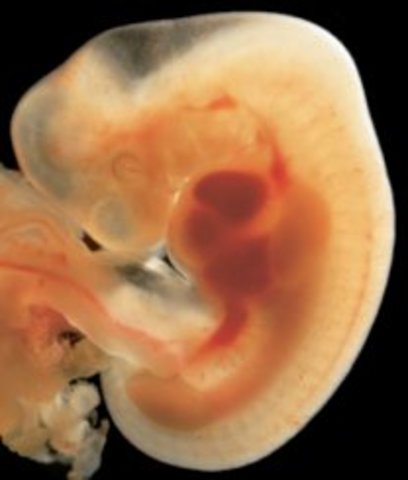

• Week 5: The Embryonic Stage Begins

Week 5: The Embryonic Stage Begins

In this stage, the placenta is beginning to form. The embryo will double in size from the week 4 embryo by the edn of week 5.

• Week 6: The Heart Begins to Beat

Week 6: The Heart Begins to Beat

Spinal cord is closing, brain is splitting into five parts, a tiny little heart forms and will begin to beat, and the arms and legs are begiining to go into place from their cells. Oxygen and nourishment will be given to the baby through its developing umbilical cord.